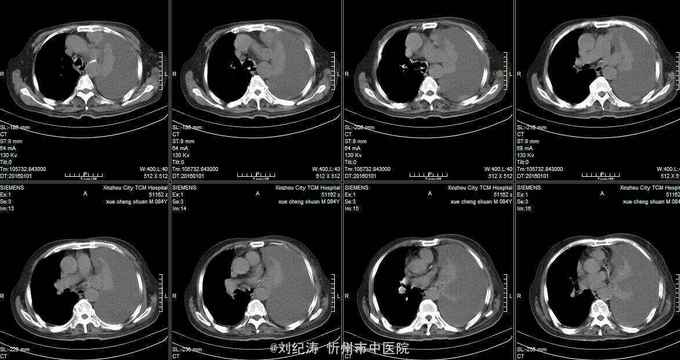

查体:ECOG评分:3分,生命指征平稳,浅表淋巴结未触及明显肿大,双眼睑无水肿,唇无发绀,颈软,双侧胸廓对称,左肺语颤增强,左肺呼吸音消失,右肺呼吸音粗,可闻及哮鸣音,心律齐,腹平软,肝脾肋下未触及,移动性浊音阴性,肠鸣音3次/分,双下肢无水肿。 辅助检查:血常规(2016.1.1):WBC:10.6*109/L,RBC:4.69*1012/L, PLT:165*109/L ,HGB:167g/L.生化(2016.1.1):谷丙转氨酶11U/L,谷草转氨酶11U/L,总蛋白60g/L,白蛋白33g/L,尿素:9.8mmol/L,肌酐:123umol/L,尿酸:251 umol/L,血糖:7.37 mmol/L;电解质:钾:4.79mmol/L,钠:123.5 mmol/L,氯:85.7 mmol/L,钙:2.03 mmol/L。肺部CT(2016.1.1):左肺完全萎缩,左侧胸腔大量积液,右肺未见异常,纵膈轻度右移,未见明显肿大淋巴结。

诊断: 1.左肺癌 左侧胸腔积液 左肺不张;2.2型糖尿病;3.低钠、低氯血症;4.低蛋白血症 治疗 完善检查,予以胸腔穿刺置管引流胸水以减轻心肺负荷,静脉给予抗感染、祛痰、止咳、平喘、提高免疫、扶正抑瘤、营养支持、调节电解质平衡及对症治疗。